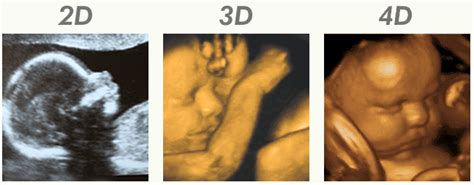

In alcuni casi può essere eseguita un’ecografia 3D o 4D. L’ecografia 3D fornisce delle immagini statiche del nascituro in tre dimensioni, consentendo una visualizzazione più dettagliata delle strutture anatomiche. L’ecografia 4D, invece, mostra immagini in movimento e in tempo reale, offrendo una "finestra" sul comportamento del bambino nel grembo materno. Verso la fine della gravidanza, i tratti del viso sono molto chiari, soprattutto se visti con la tecnologia 3D e 4D; si può vedere il viso del bambino mentre lui o lei è ancora nel grembo materno. Molti genitori richiedono questa ecografia per essere rassicurati tramite un esame del terzo trimestre. I genitori spesso ci dicono che questo è un buon modo per sentirsi più in contatto con il loro bambino prima della nascita, e li aiuta a sentirsi pronti per la nascita e la genitorialità.